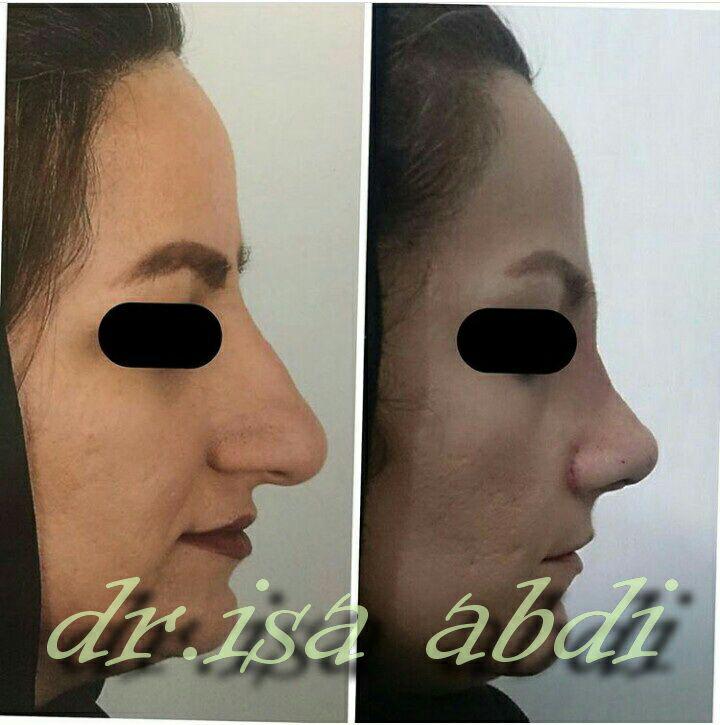

دکتر عیسی عبدی در رشت

دکتر عیسی عبدی در رشت

– متخصص جراحی فک , پلاستیک صورت و بینی

دکتر عیسی عبدی در رشت

جراحی فک , پلاستیک , صورت وبینی